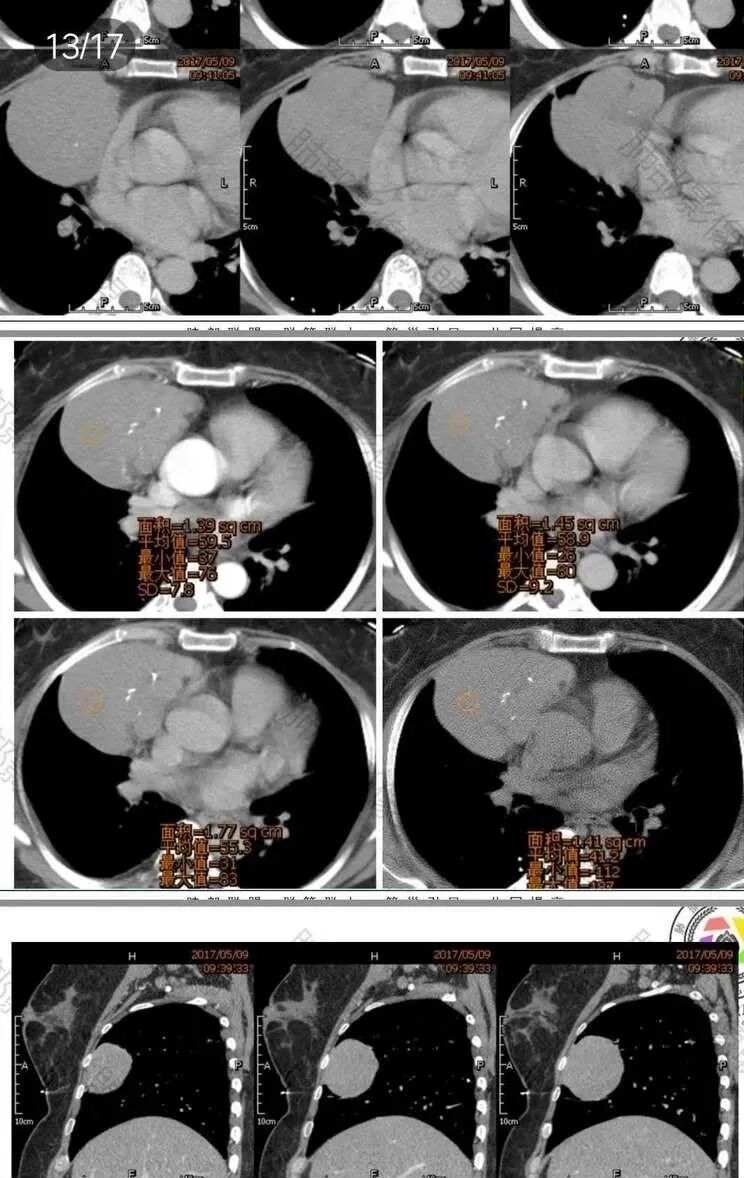

中年女性,体检发现,纵隔前外侧见不规则肿块,内见散在钙化灶,主动脉及心脏受压向后内侧轻度移位,增强后呈均匀性强化,未见明显坏死区,肺动脉延伸其中,轮廓光滑,肿块前外侧见胸膜尾。考虑胸膜来源可能性大,SFT?鉴别胸腺瘤

中年女性,体检,相邻肺组织受压,大部位于右前纵膈,貌似右侧内乳动脉增粗,肿物定位前纵膈,边界清晰,内见线样分隔及钙化,强化均匀!考虑胸腺瘤!

晨读:定位前纵隔偏右侧,病变向右侧突出,形态欠规则,与肺组织交界清楚,右肺受压体积缩小,平扫密度不均匀,可见高密度钙化,增强后可见条状强化,51岁,考虑胸腺瘤囊变,囊性畸胎瘤,鞘瘤囊变

晨读:中年女性,体检发现病变。胸部CT:纵隔右前外侧不规则肿块,内乳动脉供血、胸膜掀起,肺动脉似乎也伸入其中?主动脉及心包受压向内后侧移位,肿块分叶、内见明显分隔、散在点状钙化灶,增强后呈均匀性强化。左侧膈顶有抬高?考虑:胸腺瘤(还是选B2吧)?鉴别SFT、神经源性肿瘤、淋巴瘤等。

晨读:前纵膈占位,分叶,密度均匀,增强轻度强化,其内见钙化,内乳动脉穿行,考虑胸腺瘤AB型。

前纵隔偏右侧肿块,分叶,与心包及大血管间隙尚清晰,其内见分隔及点状钙化,轻度强化,内乳动脉供血,其内见纤细血管,无坏死及囊变,考虑胸腺瘤,AB型

晨读:女,51岁,体检发现纵隔占位。CT示右前纵隔软组织肿块,密度较均匀,内乳动脉及临近大血管受压移位,边界清晰,内部可见点状钙化,增强扫描轻度均匀强化,内部可见血管穿行,考虑纵隔来源,胸腺瘤可能,鉴别SFT

晨读:51岁女性,前纵隔偏右侧占位,分叶?密度比较均匀,肿块内部见斑点状的钙化影,增强均匀强化,体动脉供血?从年龄看排除生殖细胞肿瘤,未见明显脂肪成分,基本排除畸胎瘤,首先考虑胸腺瘤。鉴别淋巴瘤。

晨读:老年女性,右前纵隔分叶状软组织密度肿块影,内有斑点状钙化,周围脂肪间隙清晰,增强轻度均匀强化,可见线样血管穿行影。常规考虑胸腺瘤(AB型),鉴别淋巴瘤、SFT。

前纵膈偏右侧肿块,分叶,边缘清晰,内可见多发斑点状钙化,强化均匀,血管穿行,考虑胸腺瘤AB型,鉴别SFT。